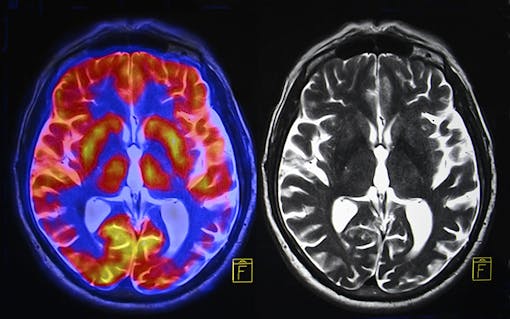

Traumatic Brain Injury, or TBI, is a serious condition usually caused by an external blow to the head that can cause severe and often chronic symptoms. These symptoms can be cognitive, behavioral, movement related, speech and visual impairing, mood altering, involve painful headaches, and even cause gastrointestinal issues.

Further, because TBI is a condition affecting a highly complex, intricate system like the brain, successful strategies will likely involve more than a single “magic bullet.”